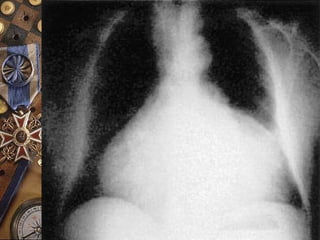

PERICARDITIS CONSTRICTIVA  50%diagnóstico patológico inespecífico  TBC  Neoplasia  Purulenta ETIOLOGIAETIOLOGIA Engrosamiento pericárdico : 1-2 cmEngrosamiento pericárdico : 1-2 cm Grosor normal : 1-2mmGrosor normal : 1-2mm

Engrosamiento pericárdico : 1-2 cmEngrosamiento pericárdico : 1-2 cm

Grosor normal : 1-2mmGrosor normal : 1-2mm

PERICARDITIS CONSTRICTIVA

NORMALNORMAL CONSTRICTIVACONSTRICTIVA

1-2mm1-2mm

1-2cm1-2cm